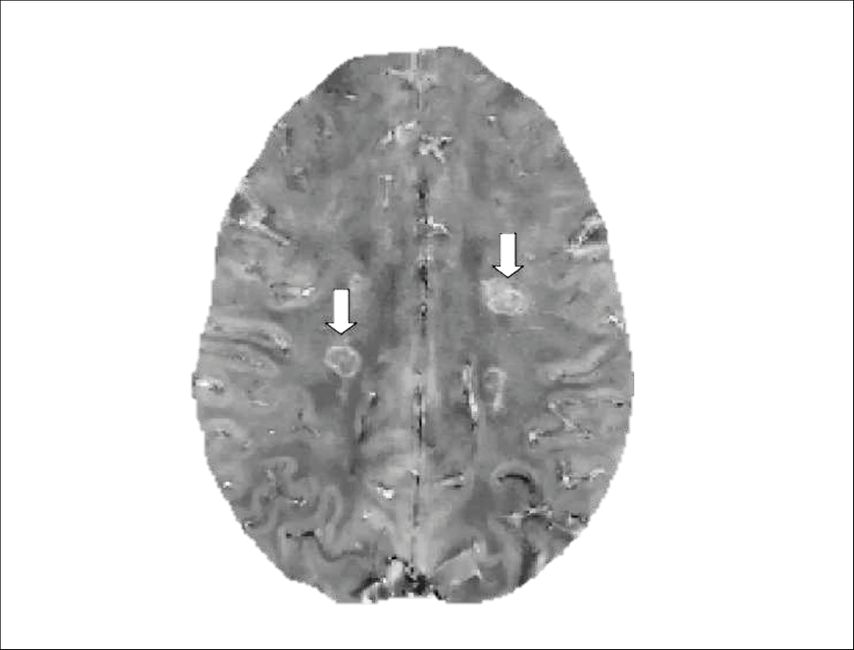

Fig. 1: Example of paramagnetic rim lesions (PRLs) on quantitative susceptibility mapping (QSM). PRLs are indicated by arrows and are characterized by a hyperintense rim reflecting iron accumulation (image modified from Cagol et al. 2023)8

On MRI, PRLs are identified using susceptibility-based sequences, such as susceptibility-weighted imaging (SWI), phase imaging, or quantitative susceptibility mapping (QSM). High-field MRI improves sensitivity, but PRLs can also be detected at 3T and 1.5T with optimized protocols.3

PRLs are the most extensively studied in vivo correlate of chronic active MS lesions. Pathologically, they reflect iron-laden microglia and macrophages persisting at the lesion edge, surrounding an inactive, demyelinated core. This spatial organization mirrors the hallmark features of chronic active lesions described in histopathological studies.